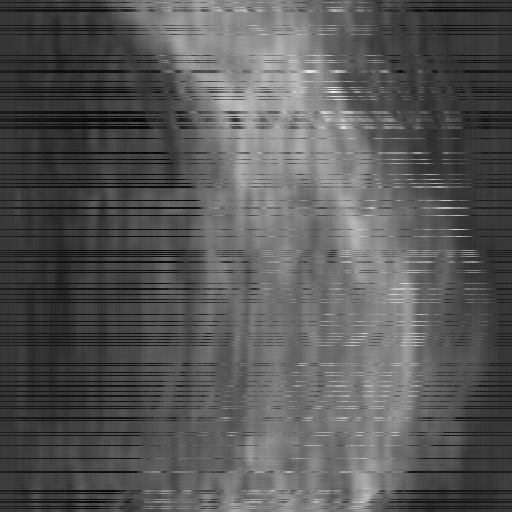

Figure 3: Qualitative completion results on TomoBank (lines 1 to 2) and LoDoPaB (lines 3 to 4) with random mask (ratio = 0.8) at 1024×\times1024 resolution. Odd columns and even columns show the sinograms and reconstructed images, respectively.

4.2.3 Completion Quality

Tab 2 summarizes accuracy results. At 2048×\times2048 resolution, HRSino achieves the best performance among all baselines while remaining memory-efficient, demonstrating its ability to extend high-quality completion to resolutions where other diffusion models fail. At 1024×\times1024, HRSino delivers accuracy comparable to its computation-intensive counterpart RePaint, showing that our optimizations do not compromise fidelity at moderate scales. Compared to DiffIR, MCG, TD-Paint, and HiDiffusion, HRSino consistently achieves higher SSIM and PSNR across mask ratios, with improvements up to +0.03 SSIM and +1.8 dB PSNR. Fig 3 visualizes sinogram completion and reconstructed images, where HRSino produces nearly indistinguishable results from RePaint. These findings confirm that HRSino fundamentally extends diffusion-based completion to 2048×\times2048 resolution in a more memory- and runtime-efficient manner.